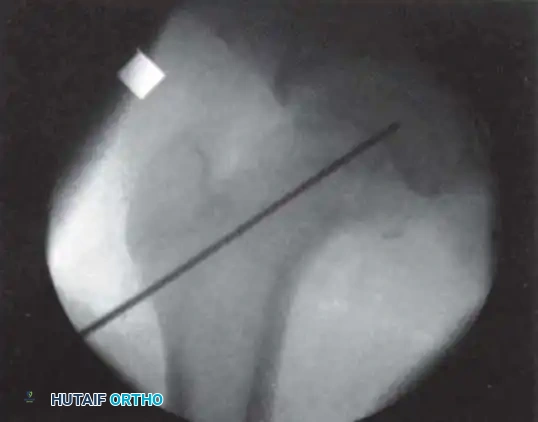

2. Fluoroscopic Setup and the "Rotating Beam" Technique

In situ pinning is fundamentally a radiographic technique. Menche, Lehman, Rab, Moseley, and Morrissy have all emphasized the absolute necessity of a rotating fluoroscopic beam.

The C-arm must be able to rotate freely through a 90-degree arc from the AP to the true lateral position without moving the patient's leg.

3. Guidewire Placement: The Morrissy Principles

Morrissy identified two common errors in SCFE pinning:

1. Passing the pin obliquely toward the anterior surface rather than the center of the head.

2. Passing the pin out the posterior neck and into the head.

To avoid this, the starting point must be selected based on the position of the displaced femoral head. The guidewire must enter the femoral neck so that it crosses the physis perpendicular to its surface and anchors in the exact center of the epiphysis.

* Because the head slips posteriorly, the starting point on the lateral cortex must move anteriorly. The more severe the slip,